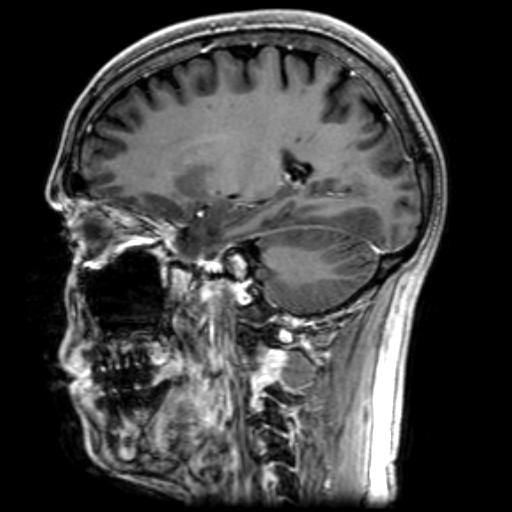

Flair Images With Enhancement Suppressed

This type of magnetic resonance imaging (MRI) study looks at the brain with 24 sagittal (vertical - front to back) cuts beginning at right side of the brain and moving to the left.

Flair images allow the signal from cerebrospinal fluid (CSF) to be suppressed so existing lesions are easier to see.

(Examples of multiple long-term lesions can be seen best on images 5.6 to 5.9 and 5.11 to 5.14)